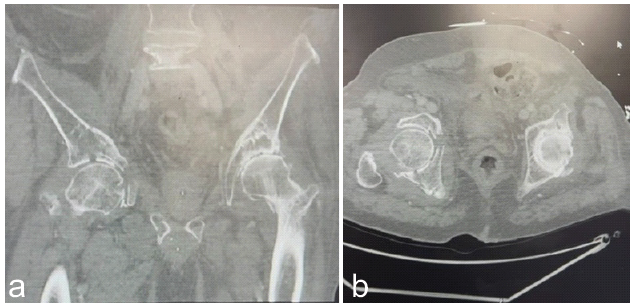

A 76-year-old male with a medical history of coronary artery disease, hypertension, hyperlipidemia, osteoarthritis of bilateral hips, osteopenia, and prior inguinal hernia repair presented to our institution 2 days after a fall from standing height. He was a daily smoker and consumed alcohol regularly. The fall resulted in multiple closed injuries, of which included a right acetabular fracture, right proximal humerus fracture, and rib fractures in right ribs 8–12. Of note, there were no neurovascular injuries recorded. His initial hospital course was complicated by rhabdomyolysis and a modestly elevated troponin level. On exam, the patient had pain while sitting and during pelvic squeeze on evaluation. The right lower extremity demonstrated intact sensation to light touch in all lower extremity dermatomes, palpable dorsalis pedis and posterior tibial pulses, brisk capillary refill, and full motor strength in the extensor hallucis longus, flexor hallucis longus, tibialis anterior, and gastrocnemius-soleus complex. He had no evidence of incontinence or bladder injury. Radiographs and computerized tomography (CT) revealed a comminuted, minimally displaced, anterior column and posterior hemitransverse fracture of the right acetabulum, along with fractures of the right superior and inferior pubic rami as seen in Fig. 1a and b.

Figure 1: (a and b) Axial and coronal images from a pre-operative computed tomography-scan of the pelvis demonstrating a right anterior column and posterior hemitransverse acetabular fracture.